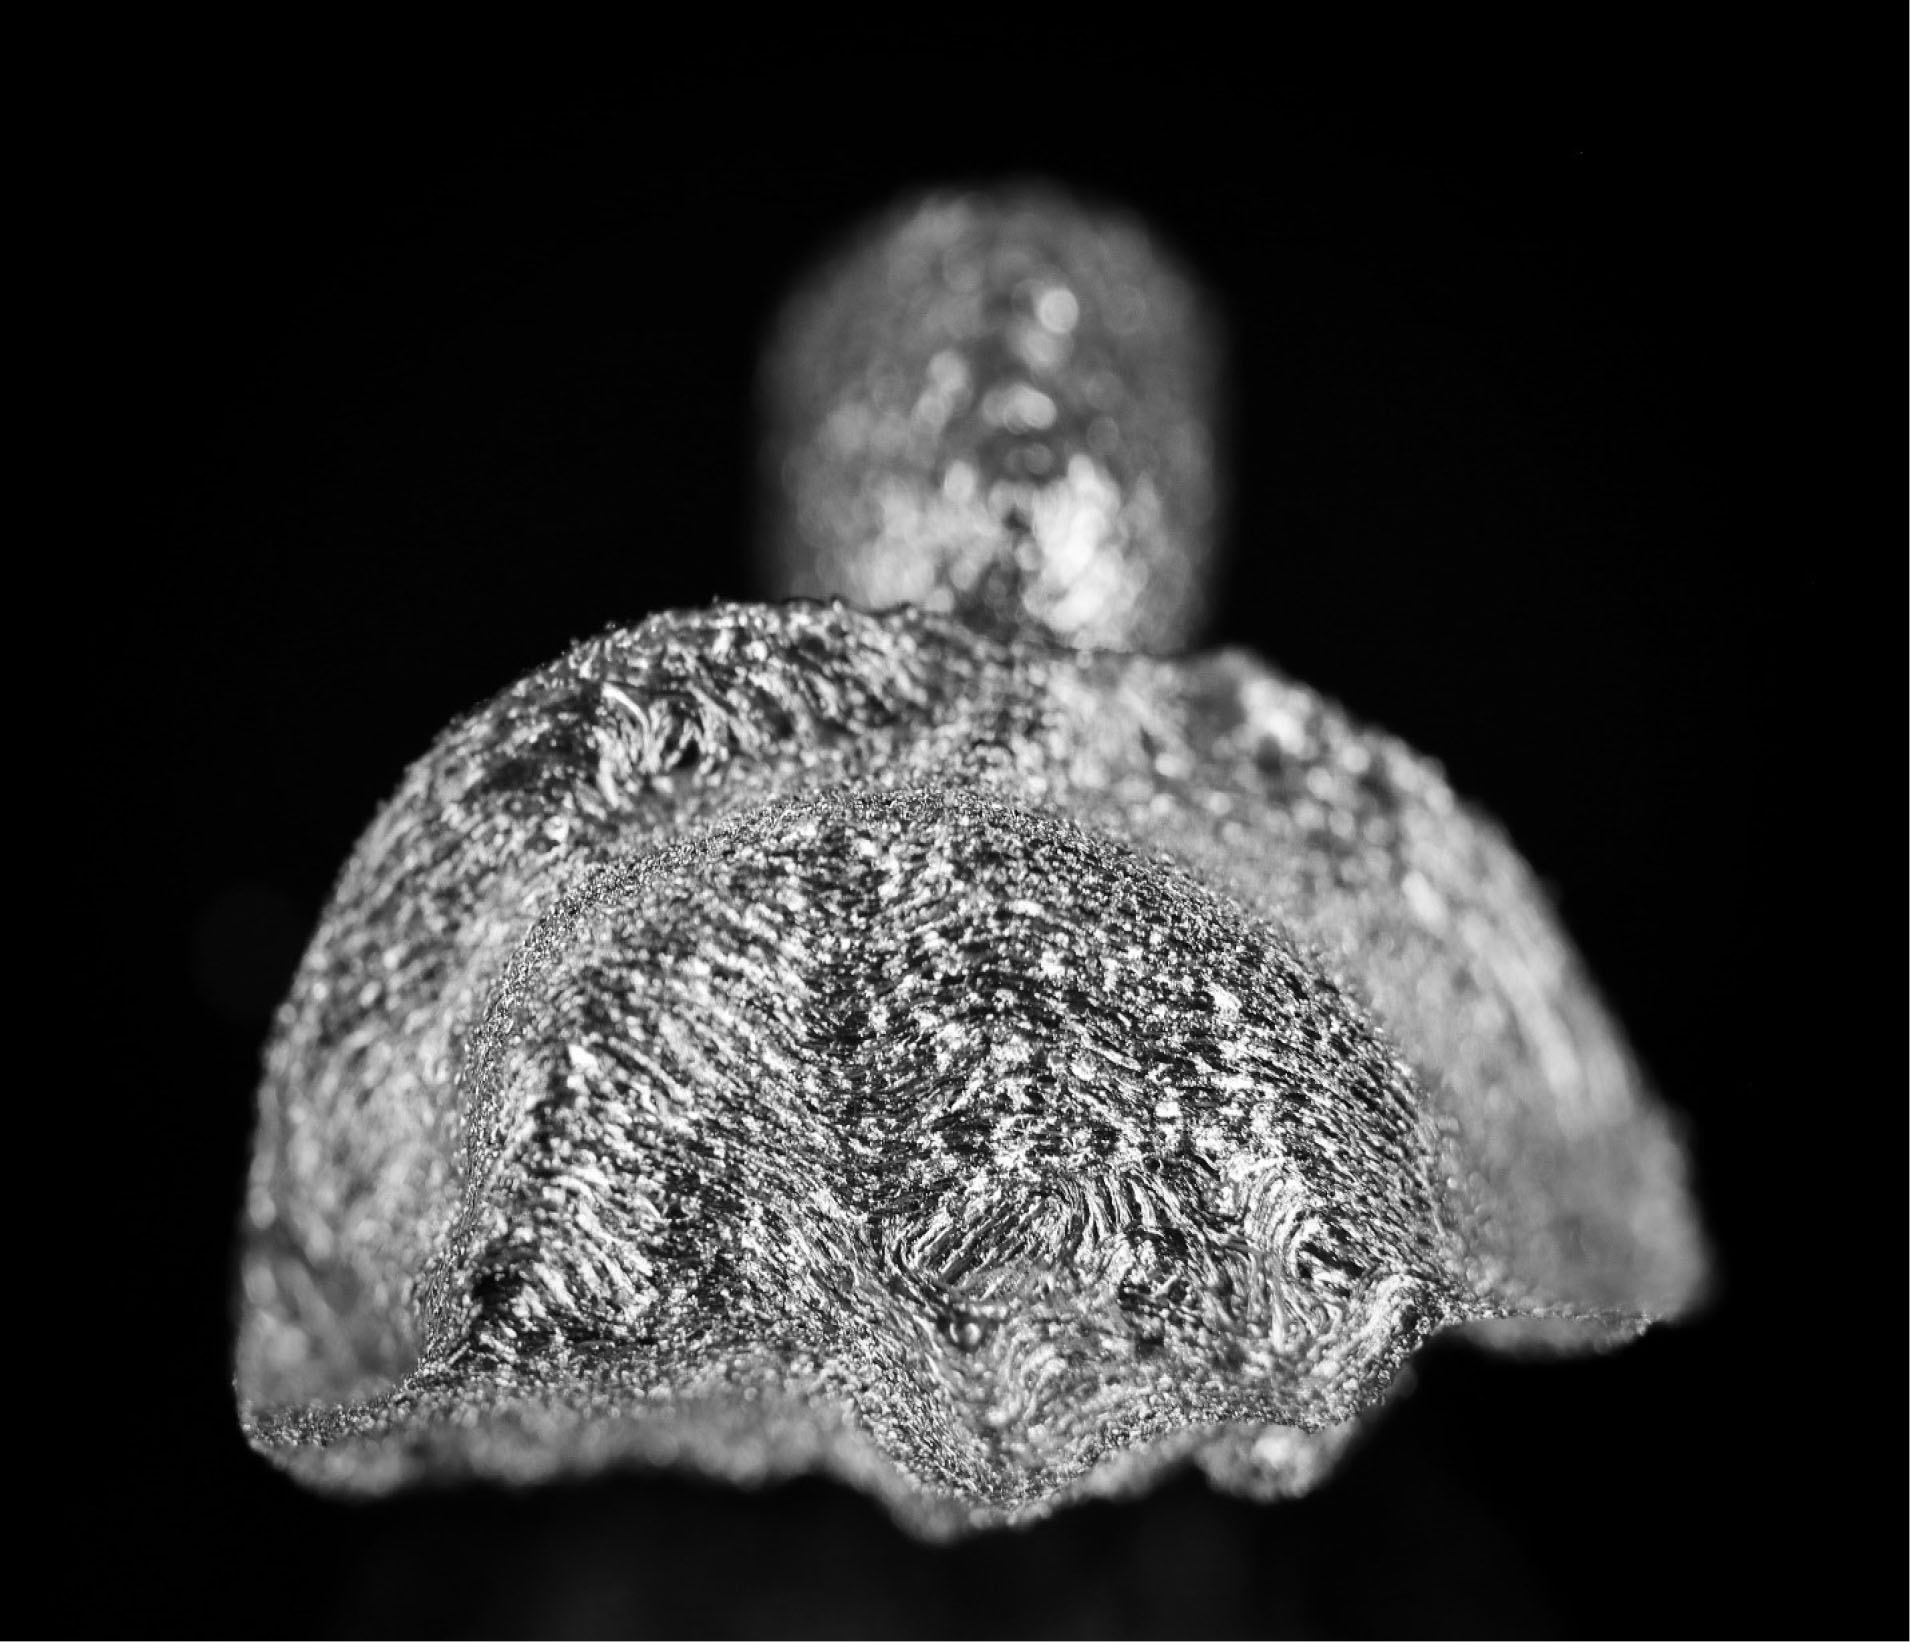

joddd-15-147-g005

Figure 5. Occlusal view of the additive-manufactured onlay.

Three extracted, undamaged human molar teeth were randomly selected from a group of extracted molars. Each tooth was fixed onto a hand-held support. A sectional tray (TempTray; Clinician’s Choice, London, Canada) and provisional material (Template; Clinician’s Choice, London, Canada) were employed to impress each tooth. The teeth were prepared for a four-surface lithium disilicate (Ivoclar, Buffalo, United States) onlay preparation (), as either a mesial-occlusal-distal-lingual (MODL) or a mesial-occlusal-distal-buccal (MODB) onlay. The provisional matrix was filled with a bis-acrylic composite resin (Integrity; Dentsply, Milford, United States) and placed over the prepared tooth. A standard four-surface provisional restoration was then fabricated, shaped, and polished (). The provisional restorations were fixed with a Pic-n-Stic (Pulpdent, Watertown, United States) and coated with titanium dioxide (3M ESPE, St. Paul, United States). The provisional restorations were then digitized (True Definition; 3M ESPE, St. Paul, United States) to create a digital stereolithography (STL) file of the provisional restoration ( and ). The STL files were digitally transferred to ADEISS (London, Ontario). The files were imported with Fusion 360 software (Autodesk, San Rafael, United States) and printed in cobalt-chromium ( and ) with a Renishaw AM 400 Laser Melting System (Renishaw PLS, Gloucestershire, United Kingdom). The printer utilized selective laser melting (SLM) technology, which melted and fused metallic powder layers (with an average diameter of 30‒50 µm) using a 400-W laser. The onlay restorations underwent standard post-processing without polishing.

The digital scanner provided an STL file of suitable resolution for three-dimensional (3D) printing in metal. The indirect onlay restorations were successfully 3D-printed in cobalt-chromium with dimensions, morphology, and fit clinically acceptable for subsequent cementation. Cementation was unremarkable and adequately retained the onlays, similar to previous investigations. 6 Marginal adaption was generally acceptable but was clinically unacceptable in one area due to an open margin. The surface finish was generally acceptable but could be improved in some areas, especially on the occlusal surface.